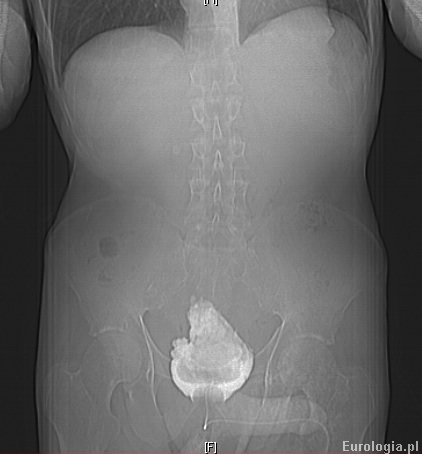

W wykonanym badaniu tomografii komputerowej jamy brzusznej stwierdzono duży złóg wypełniający w całości światlo pęcherza moczowego. W 22 dobie hospitalizacji pacjenta wydolnego krążeniowo - odedechowo z dobrymi parametrami nerkowymi przekazano do oddziału urologicznego celem leczenia przyczynowego. Ze względu na duży rozmiar zlogu zdecydowano o wykonaniu klasycznej operacji usunięcia złogu z pęcherza moczowego.

Cięciem przezprostnym w linii pośrodkowej ciała dotarto do pęcherza moczowego, przez którego ścianę wyczuwalny byl olbrzymi złóg. Cięciem podłużnym nacięto ścianę pęcherza moczowego uwidaczniając wrośnięty w śluzówkę pęcherza złóg. Ze względu na duże trudności z wydobyciem pęcherza moczowego zdecydowano o rozfragmentowaniu złogu i wyciągnięciu go w kawałkach.